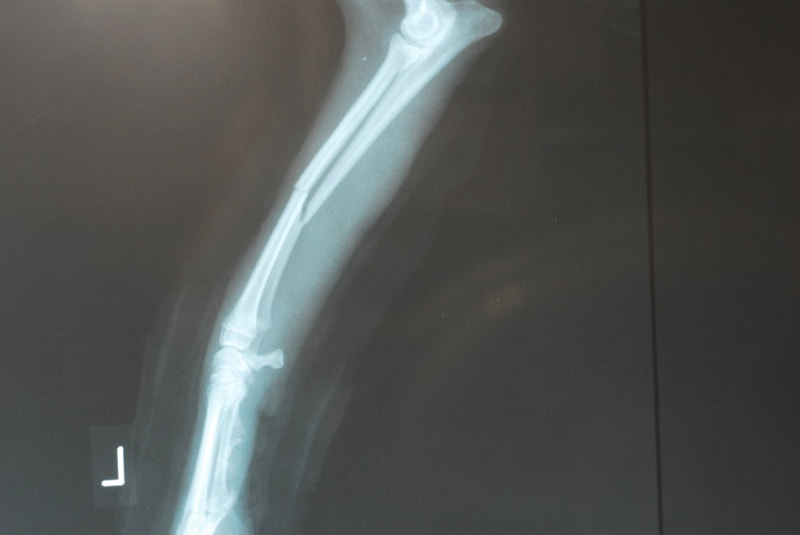

トイプードル 右遠位橈尺骨短斜骨折のALPSによる内固定